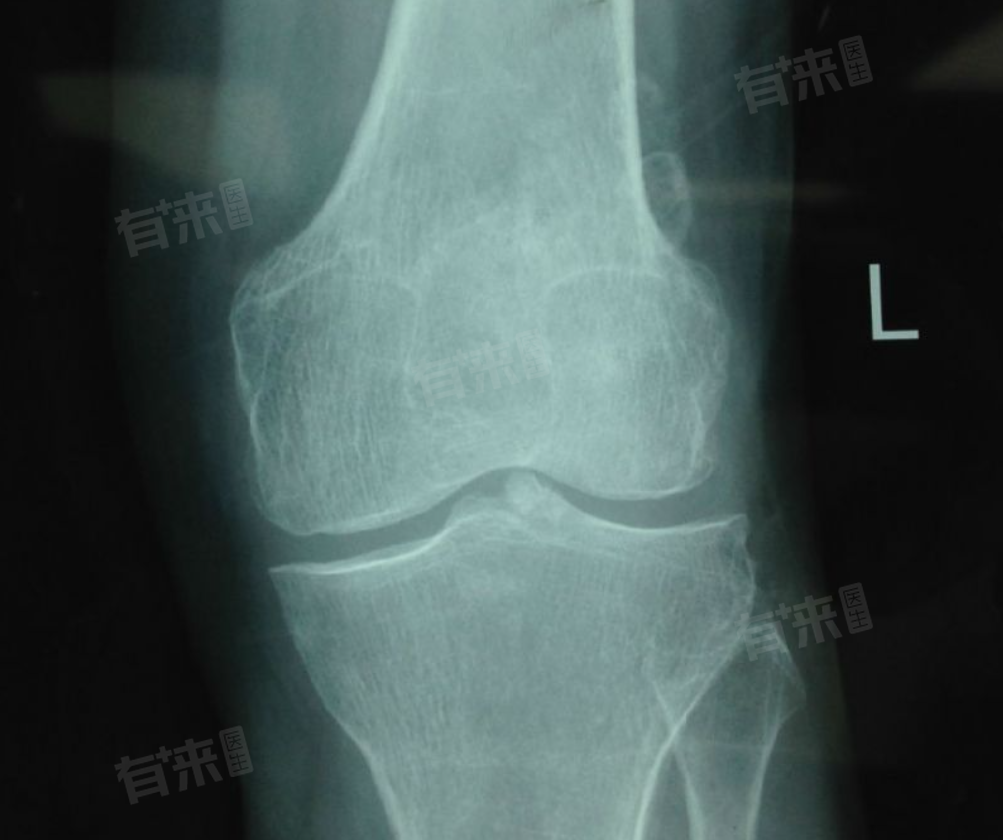

膝盖CT检查的注意事项

1、检查前准备:去除膝盖部位及其周围的金属物品,如皮带扣、拉链、金属饰品等,防止金属伪影干扰成像质量,影响诊断结果;

2、告知身体状况:务必向医生如实告知自身病史,尤其是体内是否有金属植入物,如钢板、钢钉等,以便医生判断是否适合进行CT检查及选择合适的检查参数;